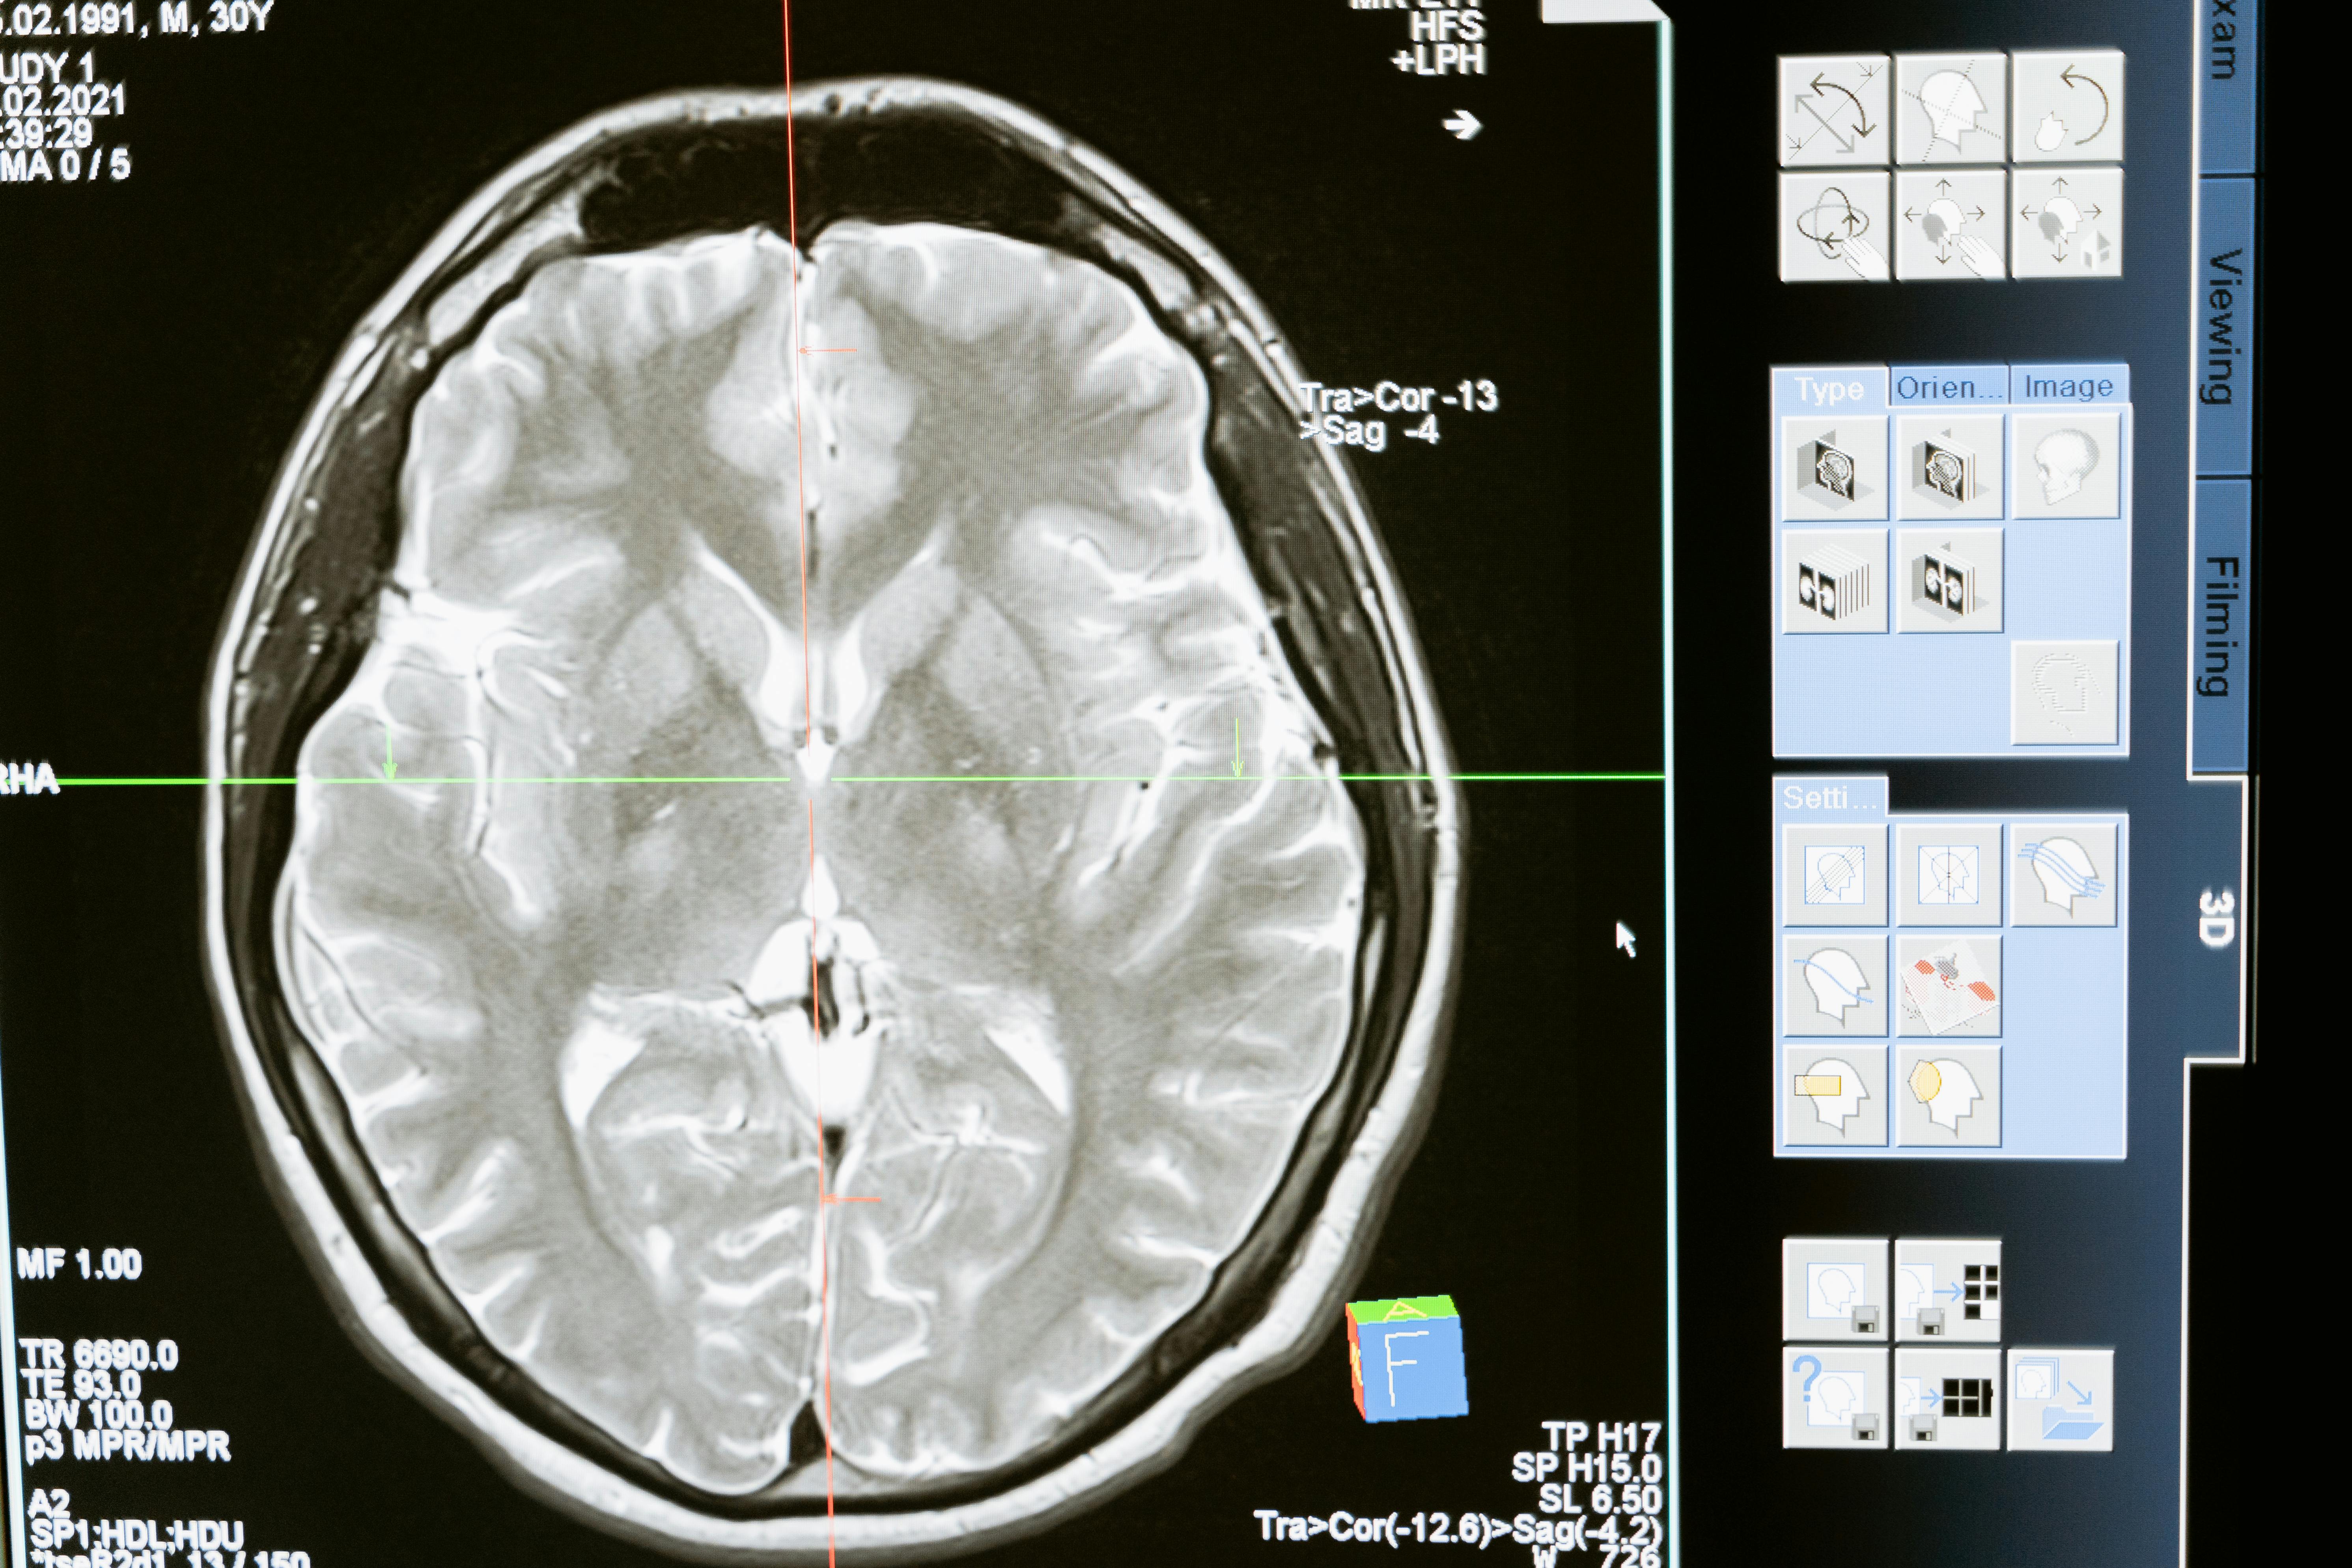

뇌출혈은 뇌 안의 혈관이 터져서 뇌 조직 내에 출혈이 생기는 상태를 말합니다. 뇌출혈은 주로 고혈압이 오래 지속됨으로써 뇌혈관 벽이 약해지고 결국 파열되는 경우가 많습니다.

실제로 국내 자료에 따르면 전체 뇌졸중 중 뇌출혈이 차지하는 비율은 약 10~15%로 알려져 있습니다. 증상은 매우 급격히 나타나며 전조증상이 없는 경우가 많고, “머리 안에서 터진 듯한 심한 두통”, 의식저하, 구토, 한쪽 팔다리 마비 등이 동반될 수 있습니다.

셋째, 정기적으로 뇌혈관 건강을 체크하고, 특히 가족력이 있는 경우 뇌동맥류 등 잠재 리스크에 대한 영상검사(필요시) 고려해야 합니다.